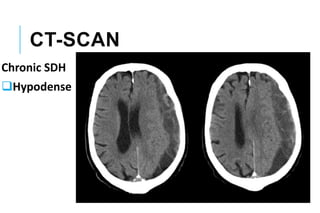

CT-SCAN

Chronic SDH

Hypodense